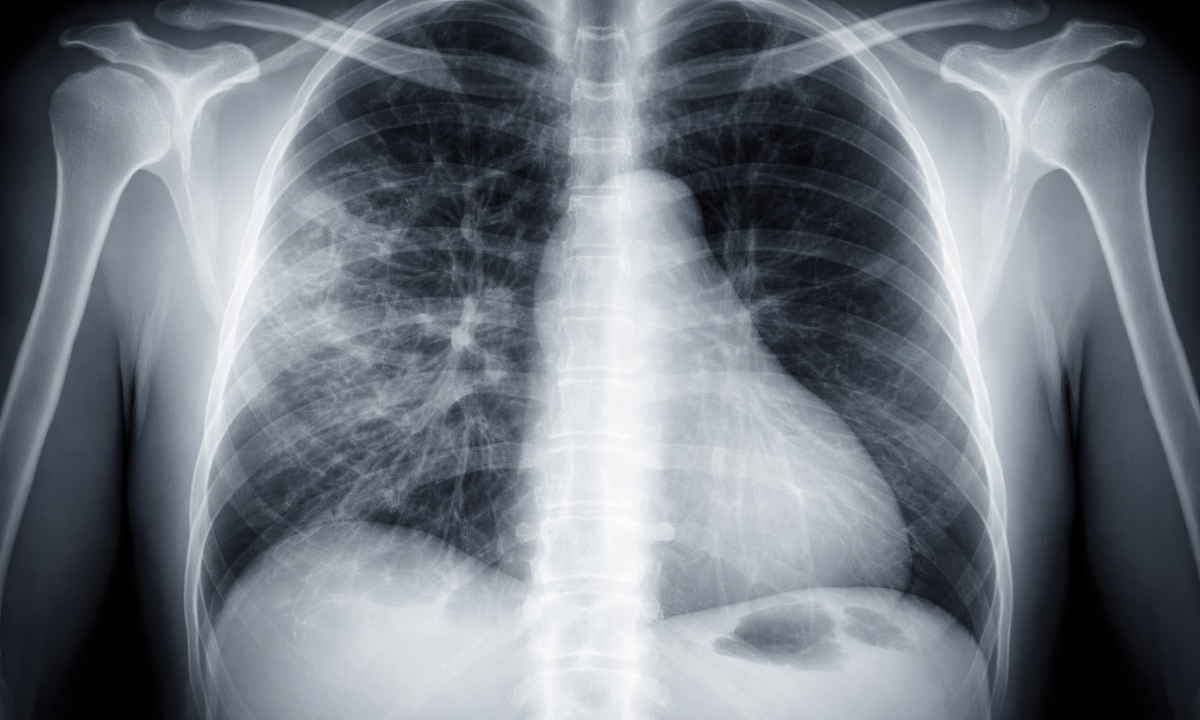

Thoracic Radiography (Chest X-Ray)

The chest X-ray is the most frequently performed radiographic procedure globally.

It acts as the primary screening tool for heart and lung conditions.

- Lungs: It detects infections such as pneumonia, tuberculosis, or fluid accumulation (pleural effusion).

- Heart: It reveals if the heart is enlarged (cardiomegaly), which can be a sign of heart failure.

- Bones: It identifies fractures in the ribs or clavicle.

An accurate X-ray chest diagnosis requires the patient to take a deep breath and hold it.

This expands the lungs fully, allowing the radiologist to see the fine details of the lung tissue and separate them from the shadows of the ribs.